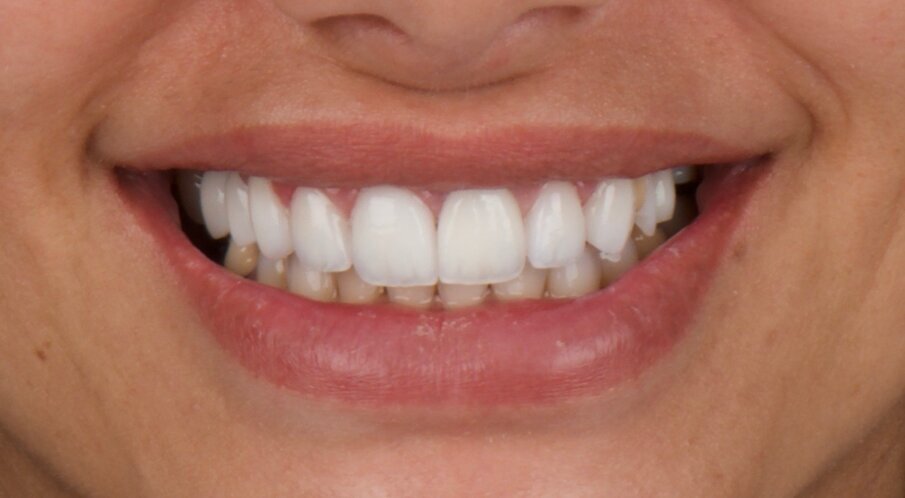

Figs. 15a & b: Pre-op (a) and post-op clinical views (b) showing an aesthetic result and healthy periodontal tissue.

Six months of healing was necessary (Fig. 14) before unscrewing the provisional restoration, taking impressions and placing the definitive screw-retained crown on to the implant. Predictable aesthetic and functional results can be obtained using the technique described (Fig. 15); therefore, a rough clinical case study should always be conducted prior to any case in order to ensure atraumatic extraction and placement of implants and bone substitute in the optimal position.

Fig. 6: Acrylic provisional restoration in place on the day of surgery.